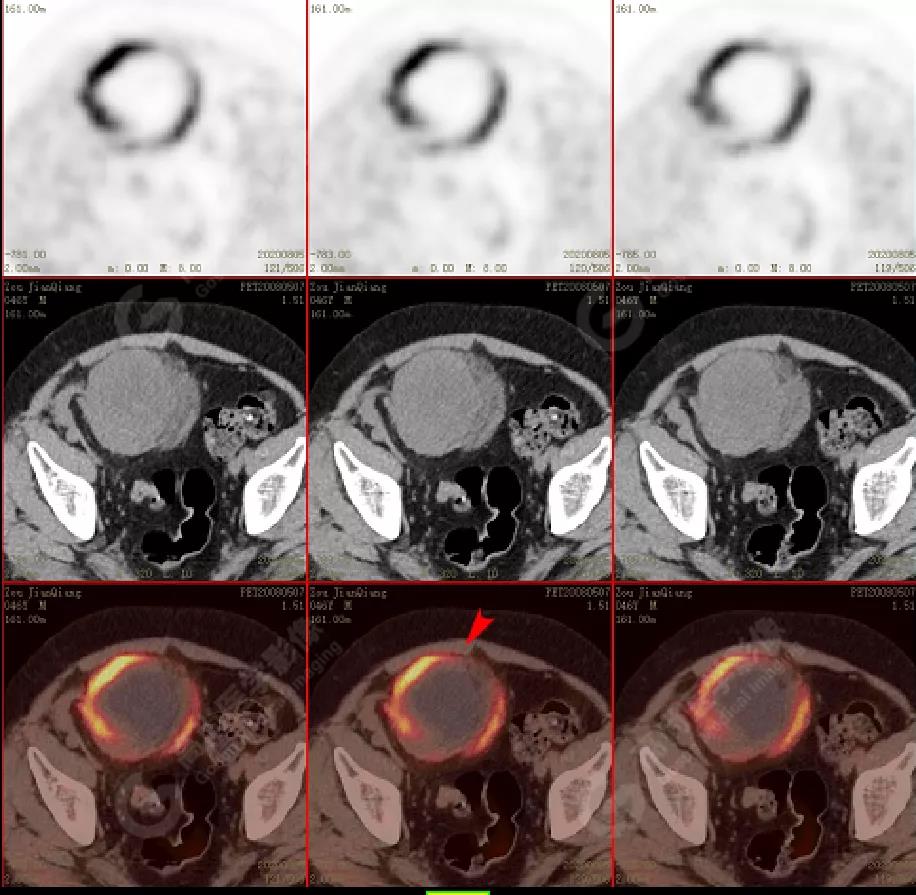

PET/CT檢查

↑移植腎下部等密度腫塊,代謝環(huán)狀增高,SUVmax13.4,中心代謝缺損

移植腎腫物穿刺活檢病理:移植后EBV陽性的彌漫大B細(xì)胞淋巴瘤。